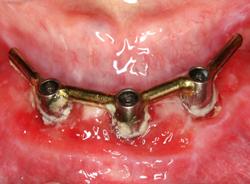

Yleisin ongelma on implanttia ympäröivän pehmytkudoksen tulehdus, perimukosiitti (kuvassa alla). Se vastaa hampaan ympärillä olevaa ientulehdusta, gingiviittiä.

Hoitona on tulehtuneen alueen puhdistuksen parantaminen, huolellinen harjaus ja hammasvälien puhdistaminen. Jos tämä ei riitä, alue voidaan puhdistaa ammattimaisesti hammashoitolassa, josta annetaan samalla kotihoito-ohjeistus.

Jos tulehdus pääsee etenemään implanttia ympäröivään leukaluuhun, syntyy peri-implantiitti. Se vastaa hampaan ympärillä olevaa kiinnityskudostulehdusta, parodontiittia. Implanttia ympäröivä luu alkaa yleensä tuhoutua kraatterimaisesti, jolloin implantin kiinnitystä menetetään.

Peri-implantiitti vaatii hammaslääkärin hoitoa. Peri-implantiitin pysäyttäminen on usein haasteellista. Huolellinen omahoito on ratkaisevan tärkeää implantin säilymiselle. Implantin menettäminen on erittäin todennäköistä, jos se on jo alkanut liikkua.

Kuvassa alla vasemmalla puolella terve hammasimplantti – oikealla plakkia ja vetäytynyt, tulehtunut ien sekä luukatoa eli peri-implantiitti.